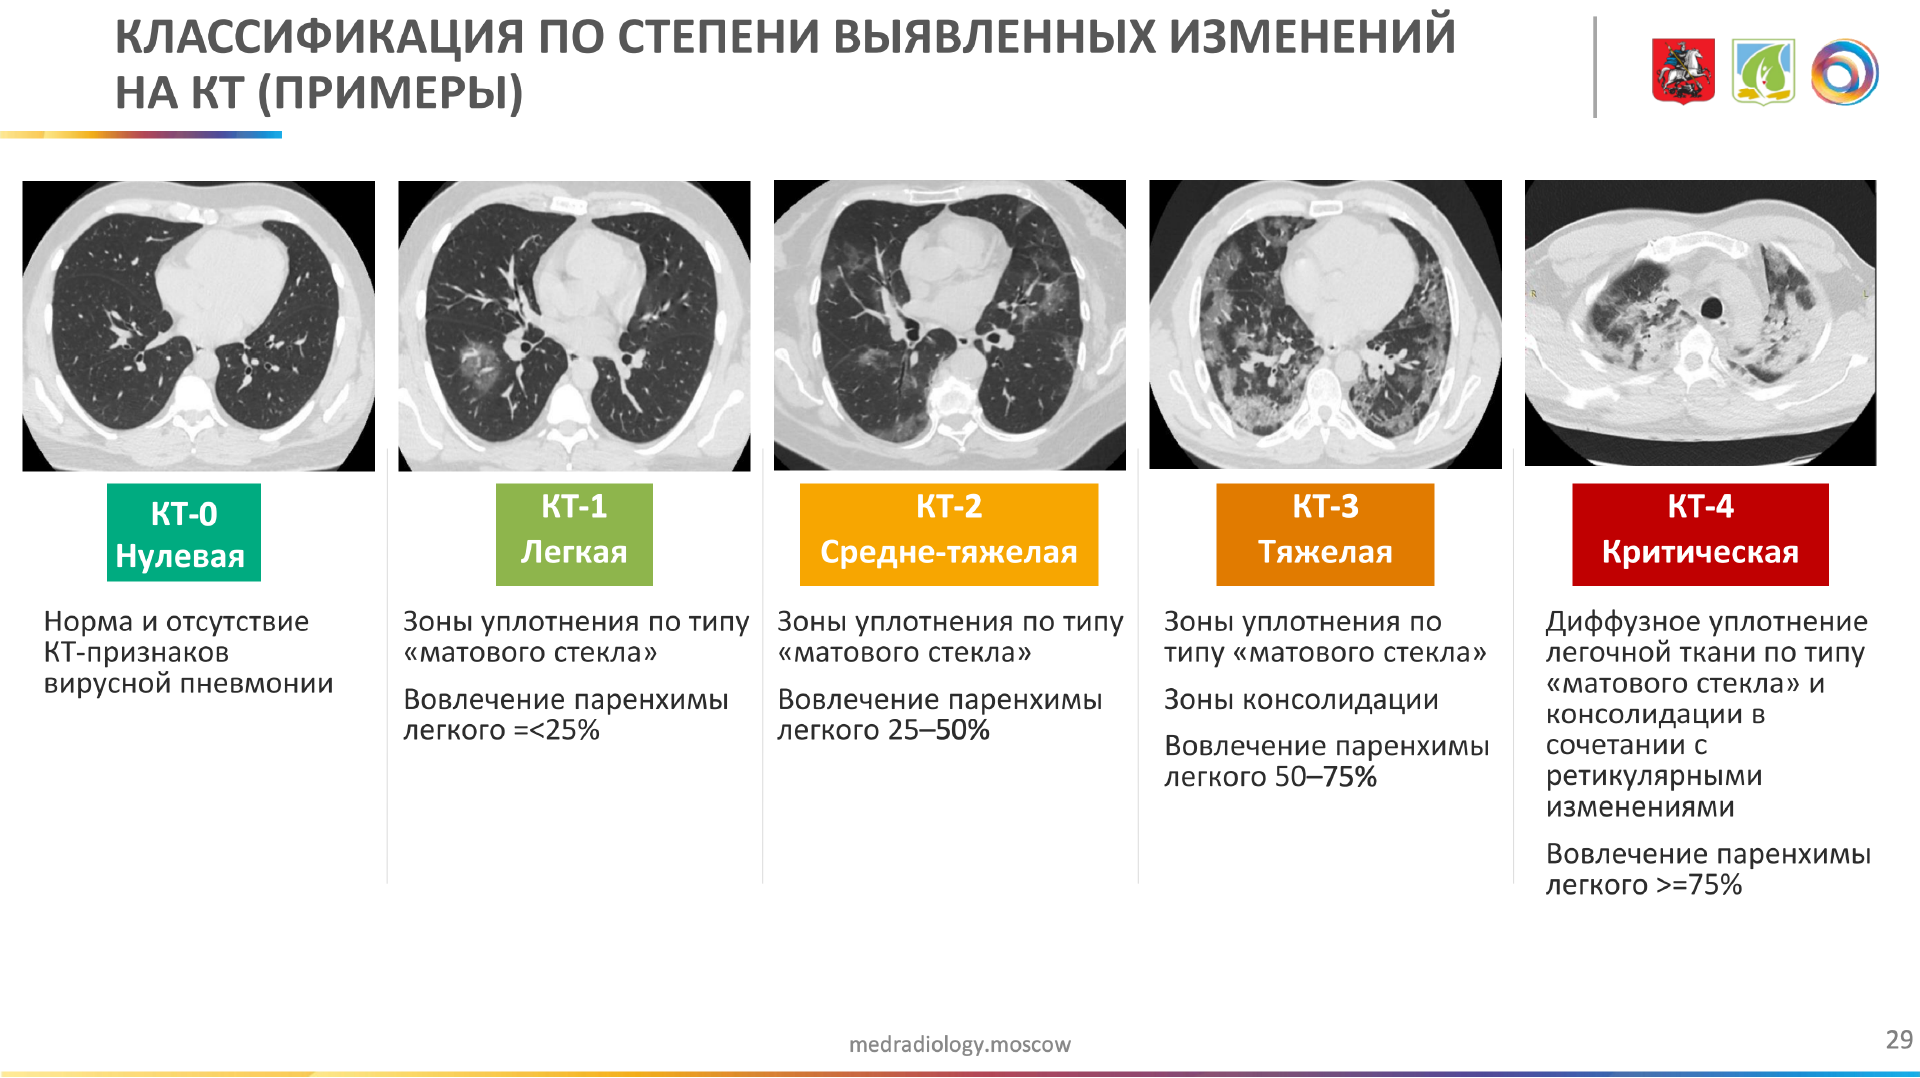

Фото рентгеновских снимков поражения легких при COVID-19

На фотографиях рентгеновских снимков видно, как вирус воздействует на легочную ткань. Характерные признаки поражения легких включают пятна, инфильтраты и наличие жидкости внутри легочных альвеол.

Фото рентгеновских снимков помогают врачам и специалистам визуально определить степень поражения легких и принять соответствующие меры лечения и поддержки пациента.